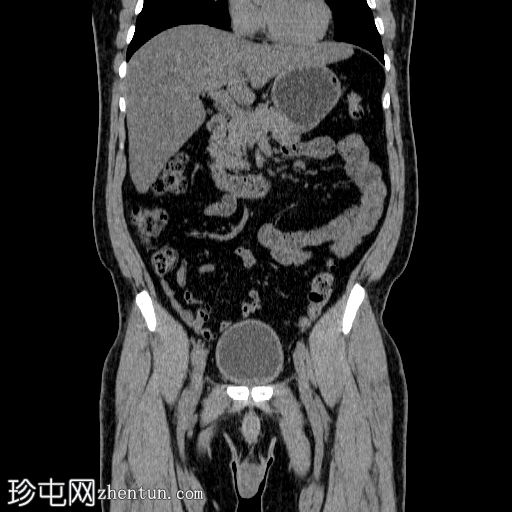

冠状位

平扫

在左侧输尿管膀胱连接处可见一枚24×15 mm的大膀胱结石。膀胱壁轻度弥漫性增厚,厚度约6 mm,提示膀胱炎。

左肾上极发现一单纯性皮质囊肿,Bosniak I 型,大小为 13 mm。

可见多个副脾(脾小体),位于主脾实质的上方和下方,在影像学各期均表现出与脾脏相似的衰减值。

肝脏弥漫性脂肪浸润。